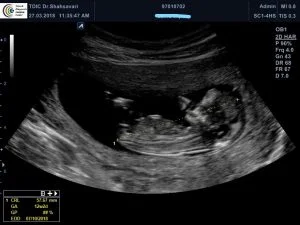

سونوگرافی روتین بارداری، رشد و حرکات جنین، تعیین جنسیت و وزن جنین، شنیدن صدای قلب جنین

سونوگرافی های تخصصی بارداری

غربالگری اول و دوم - آنومالی اسکن و انبی، انتی - بررسی چسبندگی جفت، کالر داپلر جفت، جنین و شریان رحمی، اکوی قلب جنین

اکوی قلب جنین

اکوکاردیوگرافی جنین آزمایشی شبیه به سونوگرافی است که به رادیولوژیست اجازه می دهد تا ….. ؟